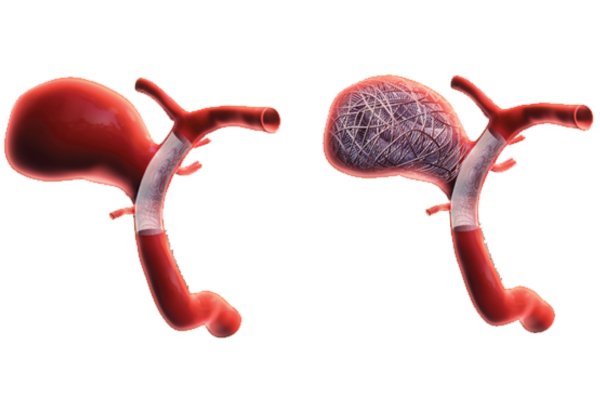

Minimally invasive technique using soft coils to block aneurysm flow, preventing rupture and ensuring long-term vascular stability.

Aneurysm coiling is a minimally invasive procedure used to treat brain aneurysms by preventing rupture. It is performed when weakened blood vessels balloon and pose a serious risk of bleeding.

Using thin catheters, soft coils are placed inside the aneurysm to block blood flow, reduce pressure, and safely prevent future bleeding.